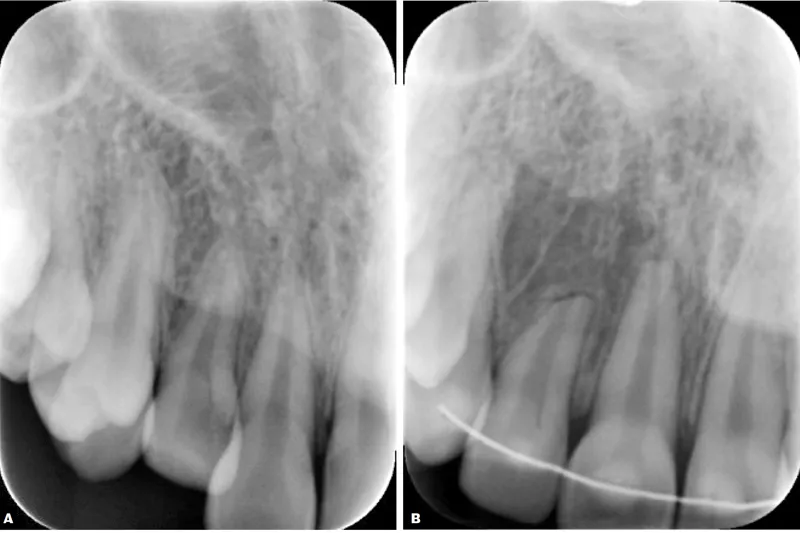

Formålet med denne artikel er at belyse patogenese, prævalens og ætiologi for ortodontisk induceret inflammatorisk rodresorption (OIIRR). Artiklen er baseret på en litteraturgennemgang af tidligere publikationer vedrørende rodresorptioner efter ortodontisk behandling. OIIRR er en bivirkning til de vævsreaktioner, der resorberer en iskæmisk zone, som dannes omkring tandens rod (“hyaliniseret zone”) efter påvirkning med ortodontiske kræfter. Overkæbeincisiverne er den tandgruppe, der har størst risiko for at udvikle OIIRR. Forekomsten af små OIIRR uden klinisk betydning er 32-96 %. Forekomsten af alvorlig OIIRR er 1-5 %. Ætiologien for OIIRR er kompleks og multifaktoriel, og der findes mange prædisponerende faktorer såsom individuel modtagelighed og faktorer, som er relateret til den ortodontiske behandling.

This article is based on a literature review of studies regarding root resorption after orthodontic treatment. OIIRR is a side effect of tissue response in order to resorb an ischemic zone formed around the root of the tooth (“hyalinized zone”), initiated by orthodontic forces. Upper incisors have the highest risk of developing OIIRR. The presence of minor, clinically irrelevant, OIIRR is 32-96%. The occurrence of severe OIIRR is 1-5%. The aetiology is complex and multifactorial and there are many predisposing factors for OIIRR such as individual susceptibility and factors induced by orthodontic treatment. During orthodontic treatment, it is therefore important to pay attention to the anamnesis and diagnostics of the patient, as well as understanding how the orthodontic treatment procedure should be optimized in order to reduce the risk of severe root resorptions.